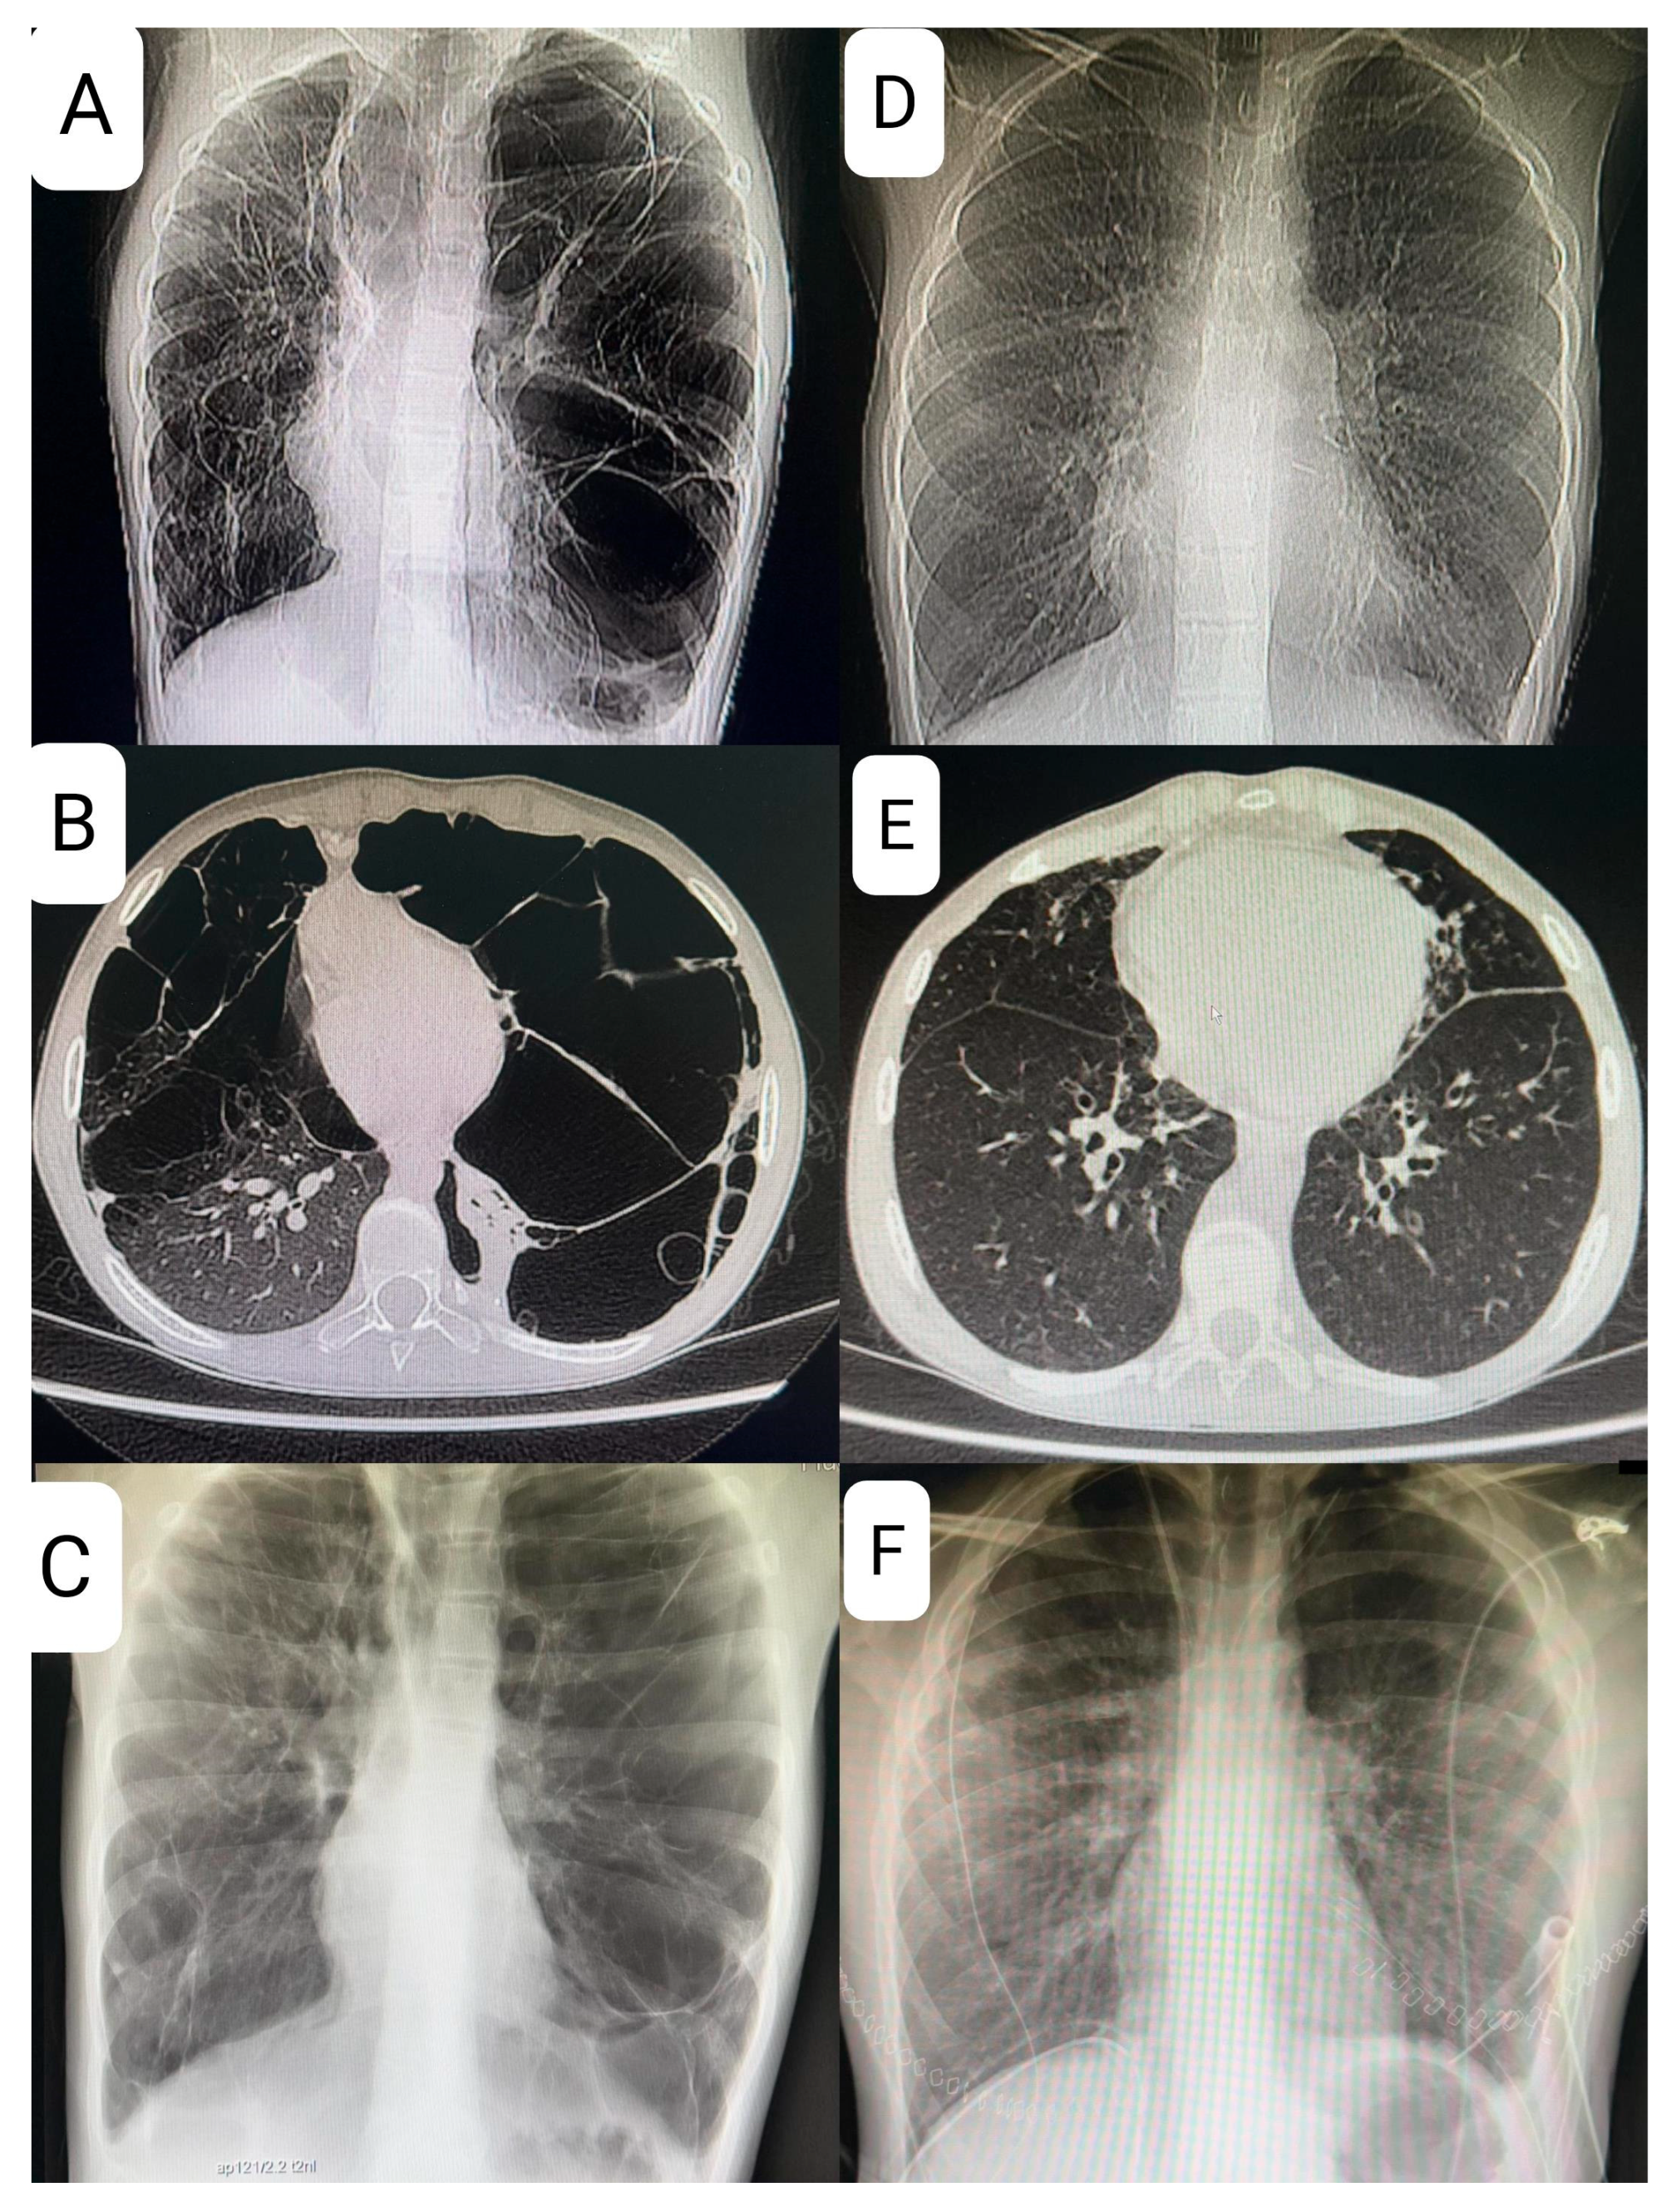

At age 9, the patient presented with shortness of breath and decreased exercise tolerance, leading to a diagnosis of left-sided pneumothorax, followed by a recurrence of pneumothorax several weeks later and the need for pleurodesis. Magnetic resonance imaging (MRI), X-ray, and computed tomography (CT) of the chest revealed multiple lung cysts, and BHDS was confirmed by genetic testing (Figure 3).

In November 2022, the patient was hospitalized for shortness of breath and cough due to pneumonia. Imaging studies showed parenchymal-interstitial infiltrates and progression of cystic changes, with a rightward mediastinal shift.

The patient’s lung disease was considered to be severe, and given the lack of effective pharmacotherapy, the patient was considered for LTx after all contraindications were excluded. Reevaluation in early 2024 confirmed advanced cystic degeneration with extensive bullae, areas of fibrous thickening, and reduced vascular architecture—all of these findings were considered life-threatening. A 6 min walk test showed significant exercise desaturation, which, together with findings mentioned above, prompted placement on the list for DLTx.

The hallmark of BHDS on high resolution computed tomography (HRCT) is the presence of cysts with irregular shapes and varying sizes and numbers, with the surrounding normal lung parenchyma remaining intact. However, the mere presence of these cysts is insufficient for a confident diagnosis. In our case, a CT scan showed significant progression of cystic changes in the lungs with displacement of the heart. In patients with BHDS, the number of cysts ranges from a few to about 400, but most patients have fewer than 20 cysts and occupy less than 30% of the lung volume [6]. Cyst expansion and rupture have been documented with changes in atmospheric pressure, such as flying [5]. Since cystic lung disease rarely affects lung function in BHDS, regular follow-up with pulmonary function tests is not recommended. However, patients with cystic lung disease who have impaired lung function should have periodic testing from the beginning of diagnosis. As of today, there is no specific treatment for BHDS-associated cystic lung disease and no reports on the efficacy of mTOR inhibitor treatment [7]. In Birt–Hogg–Dubé syndrome, inactivation of the FLCN tumor suppressor gene leads to dysregulation of the mTOR signaling pathway, which plays a central role in the control of cell proliferation and survival, promoting neoplastic transformation in renal tissue and the development of pulmonary cysts. This has positioned the mTOR axis as a possible therapeutic strategy in BHDS.

Figure 3. (AC)—preoperative images—large cysts and shift of the mediastinum to the right; (A): CT topogram, (B): CT transverse section, (C): X-ray p–a; (DF)—postoperative images—normal lung tissue; (D): CT topogram, (E): CT transverse section, (F): X-ray.